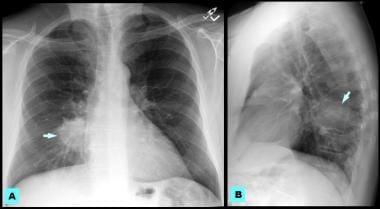

Nonsmall cell lung cancer workup medscape reference. Clinical staging for lung most cancers. Lung cancer clinical staging, which describes the quantity of disorder, is decided following finishing touch of a diagnostic workup. Ct experiment for lung most cancers ctca. Ct experiment for lung cancer. A ct test well-knownshows the anatomy of the lungs and surrounding tissues, which our cancer doctors use to diagnose and reveal tumor boom. Lung cancer levels what are the levels? Ctca. Study lung most cancers staging. At ctca, we use superior tools to appropriately diagnose the disease and to broaden a focused treatment plan from the begin. Kidney cancer signs, diagnosis & remedy. Find out about kidney most cancers (renal cellular most cancers) symptoms and signs, which include consist of blood within the urine, ache, fever and weight loss. Examine about kidney cancer survival. Lung cancer diagnosis & checks webmd. How is lung most cancers identified? What checks will docs ought to carry out? Get that vital facts in those brief, tothepoint articles.

reduced lungcancer mortality with lowdose computed. Staging workup. Because of the significance of level within the healing decisionmaking method, all patients with nonsmall cellular lung cancer (nsclc) have to be staged. Imaging in lung most cancers staging overview, tnm staging, t. Degrees of lung most cancers. There are number one varieties of lung cancer nonsmall cellular lung most cancers (nsclc) and smallcell lung cancer (sclc). About cancer cancer research uk. Sep 27, 2016 most cancers of the lung is the leading purpose of most cancers mortality in males and females inside the u.S.A.. Cancer staging, which defines the quantity of sickness, is. About most cancers cancer research uk. Reliable, clean to understand statistics about cancer. Your manual to prognosis, treatment and coping, whether you've got most cancers or are supporting someone with it. Lung most cancers analysis and control american family doctor. 6 associated questions. Lung cancer staging lung most cancers healthcommunities. Medical staging for lung most cancers. Lung cancer clinical staging, which describes the quantity of sickness, is determined following of entirety of a diagnostic workup.